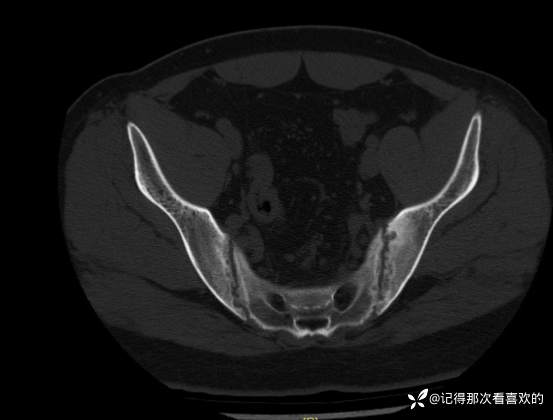

06-04 胸部CT平扫|骶髂部CT平扫:1、双肺下叶少许慢性炎及纤维灶,部分呈间质性改变可能。2、左肺下叶小结节,随诊。3、扫及脂肪肝。4、扫入胸椎椎体毛糙略呈竹节样改变,请结合临床。5、骶髂关节异常改变,考虑骶髂关节炎,强直性脊柱炎可能?请结合临床及相关检查,随诊。

06-05 骶髂关节MRI平扫:1、双侧骶髂关节改变,符合为强直性脊柱炎所致。请结合临床实验室检查结果。2、左髋关节少量积液。请结合临床及其他检查,随诊。